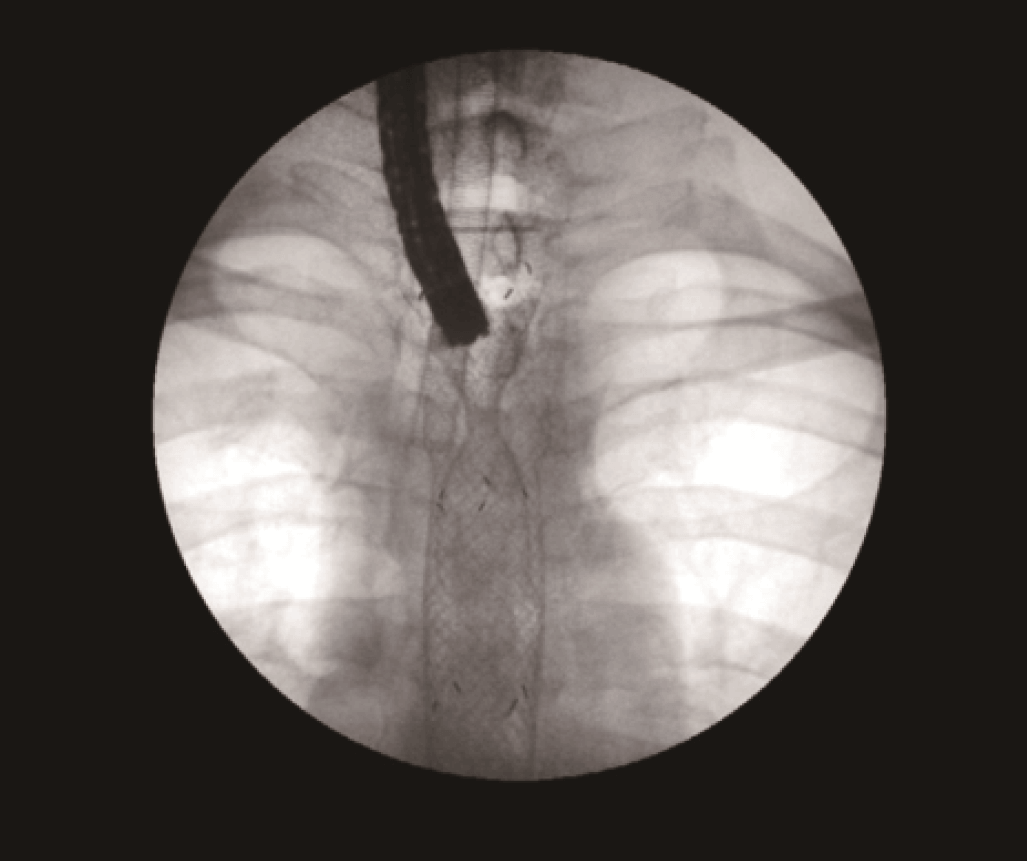

To open the stricture, an 18 mm x 80 mm fully covered esophageal HANAROSTENT was introduced. The accurate placement of SEMS in the proximal esophagus is usually challenging.

However, the three marks at the HANAROSTENT’s distal, medial and proximal ends were easily seen under fluoroscopic guidance, and were valuable in ensuring acurate deployment, just distal to the upper esophageal sphincter (Figure 5). The distal end of the HANAROSTENT remained in the patent portion of the previous stent. The endoscopic view of the SEMS proximal end can be observed in the images below (Figures 6, 7 and 8).